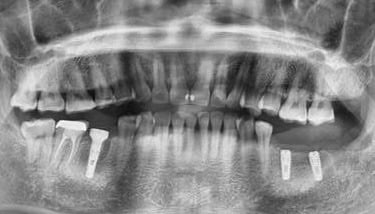

Reabilitare orala prin inserare a 3 implanturi dentare la nivelul cadranului II. In acelasi timp chirurgical s-a realizat aditie osoasa prin elevatia mucoasei sinusale in vederea asigurarii suportului osos necesar aplicarii implantului posterior.

Inserare 2 implanturi in cadranul III si un implant inserat post-extractional in cadranul IV